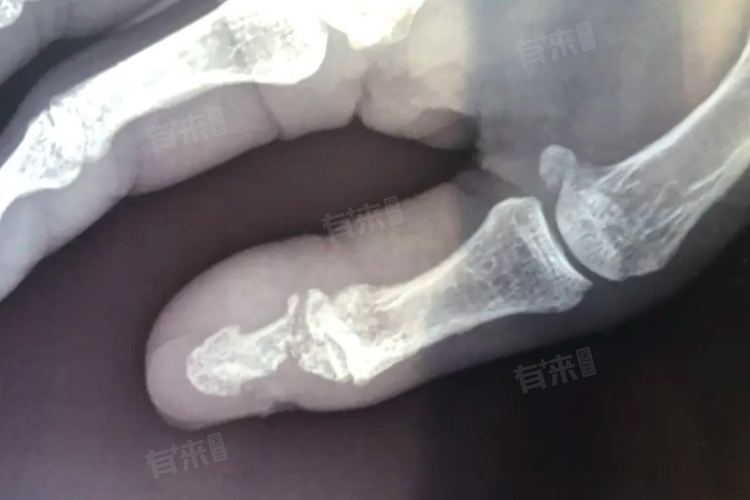

- 如果大拇指骨折属于稳定性骨折,如裂缝骨折或轻度的移位骨折,骨折断端之间的接触面积较大,且相对稳定,这有利于骨折的自愈。在这种情况下,骨折断端的骨膜通常保持相对完整,骨膜内含有丰富的成骨细胞和血管,能够为骨折愈合提供重要的细胞来源和血液供应。只要给予适当的固定,减少骨折断端的微动,人体自身的修复机制就有可能使骨折逐渐愈合。

- 然而大拇指骨折也并非都能自愈,还存在一些影响因素。如果骨折移位明显、粉碎性骨折或伴有严重的软组织损伤,自愈的难度就会增加。因为这类骨折会破坏骨折部位的血液供应,导致骨折断端之间的接触不良,影响骨痂的形成和骨折的愈合。